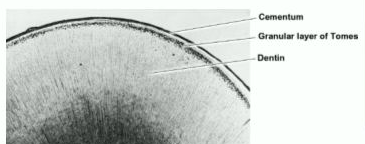

1. Granular layer of Tomes

1. Only seen in ground sections

1. Black "dots" at CDJ

1. Small air spaces due to root dentinal tubules slow rate of secretion